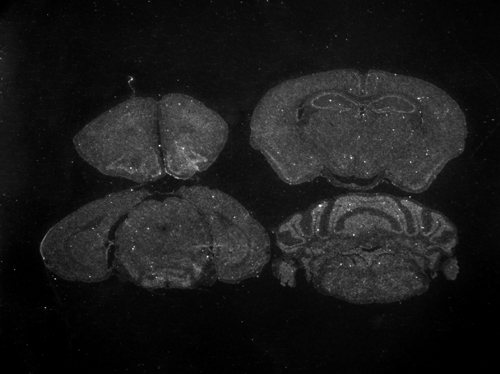

Mice homozygous for a knock-out allele exhibit progressive storage pathology in the CNS and peripheral organs, glycosaminoglycan accumulation in brain and most somatic organs, lysosomal distension and dysfunction, astrocytosis, microgliosis, hepatosplenomegaly, behavioral deficits and premature death.